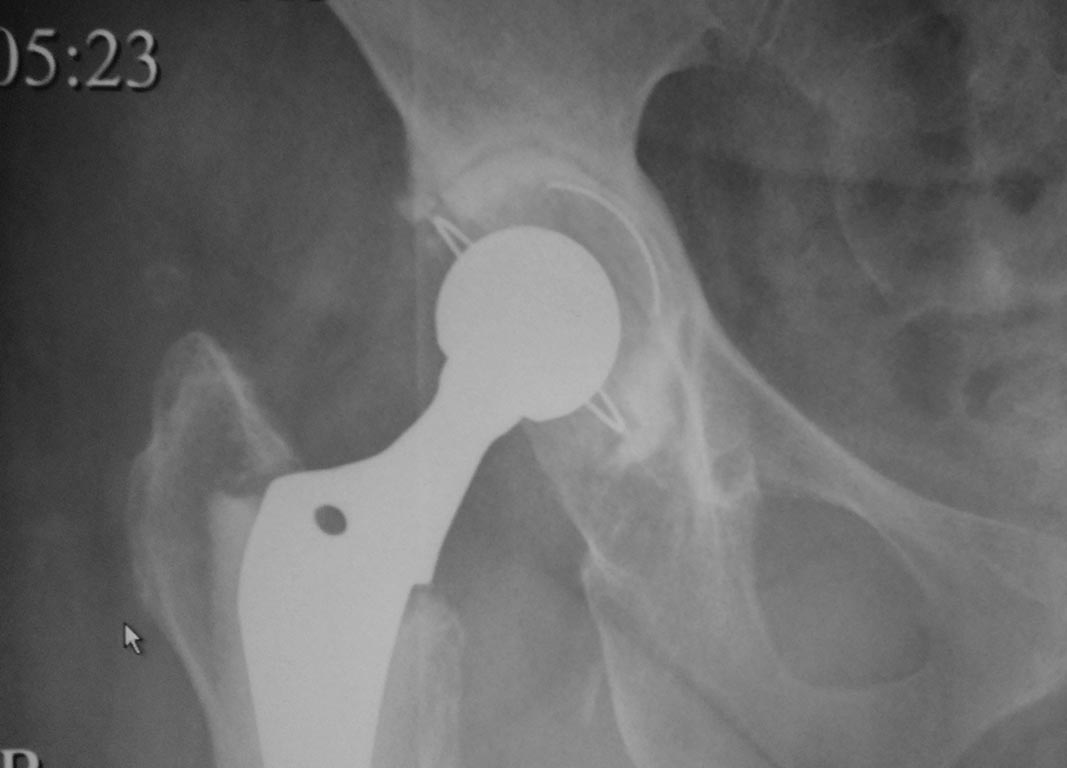

Вертлужная впадина заполнена хрящевым дебрисом, ее дефектов и дефекта заднего края нет.

Покрытие чашки отличное.

Антеверсию выставили не более 10 град, больше - вывих.

Латеральную пластину визуализировали, но чашка с ней не конфликтовала.

При планировании вмешательства были готовы имплантировать вертлужный компонент безцементной фиксации, но интраоперционно убедились, что качество тазовой кости не позволит с хорошим press-fit'ом имплантировать безцементную чашку.

Нашему пациенту 60 лет